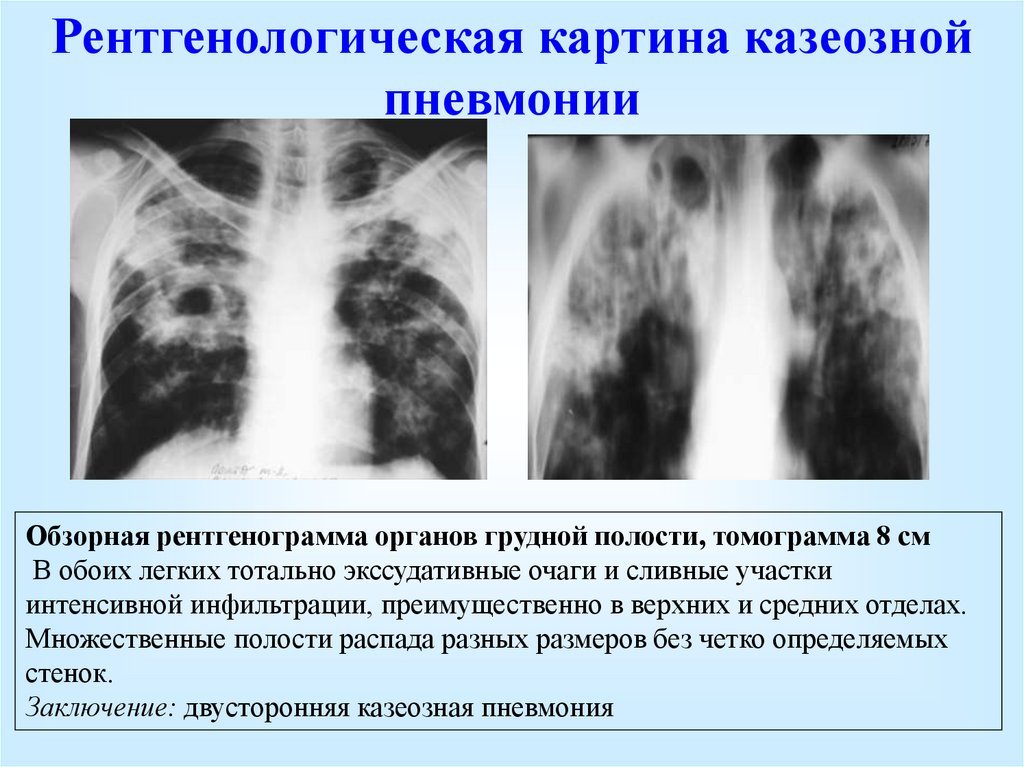

Очаговый и инфильтративный туберкулез презентация - 94 фото